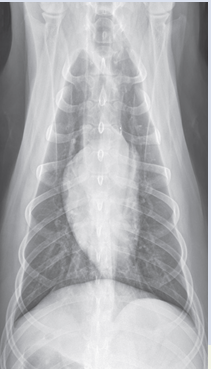

VD

Expiration